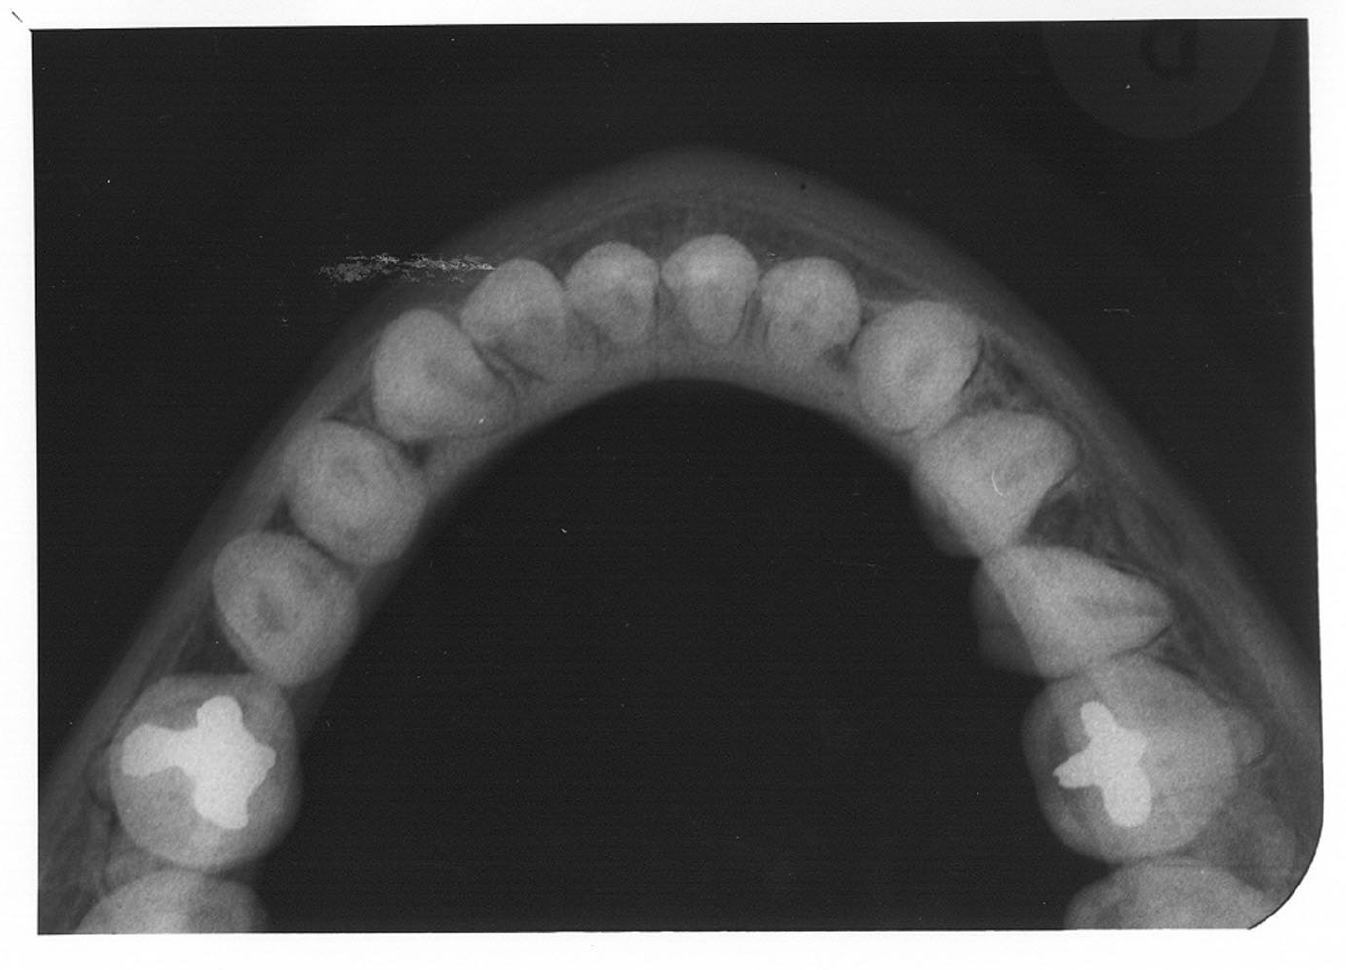

Occlusal Radiographic Images

Occlusal radiography is a supplementary radiographic examination designed to provide a more extensive view of the maxilla and mandible.

The occlusal image, as seen in Figure 3, is very useful in determining the buccolingual extension of pathologic conditions and provides additional information as to the extent and displacement of fractures of the mandible and maxilla. Occlusal radiographic images also aid in localizing unerupted teeth, retained roots, foreign bodies, and calculi in the submandibular and sublingual salivary glands and ducts. It should be noted that when imaging soft tissues, exposure time needs to be appropriately reduced.

Figure 3 - Occlusal Images

Figure 3